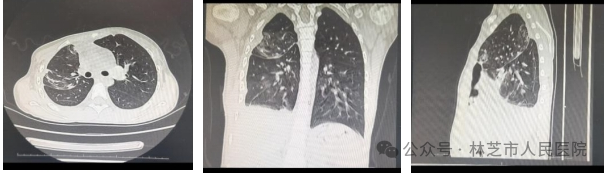

图片

▲3月29日复查胸部CT